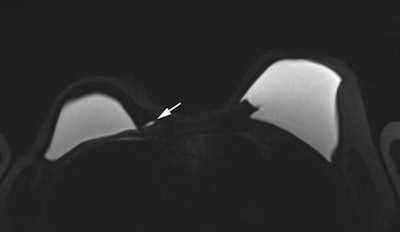

Rather than a clear rupture, a "perspiring" implant, where gel slowly leaks through the porous membrane, is the most common problem that surgeons report, according to Dr. Corinne Balleyguier, head of breast imaging in the department of radiology at the Institut Gustave Roussy (IGR)in Villejuif, France.

"Perspiration can't be confirmed or assessed by ultrasound, but it accounts for 60% of problems related to defective implants," she commented. "Ultrasound may depict a slight fluid slick around the implant, but this might be normal breast fluid or perspiring gel."

In research involving 270 implants removed at the IGR, MRI with dedicated silicone sequences was helpful in diagnosis of perspiration. In the 93 perspiring implants, 43 out of 49 ultrasound exams were normal, with six false positives for rupture. Sixteen MRI examinations were also performed on the 93 perspiring implants. Seven out of nine MRI exams showed perspiration because MRIs were acquired with silicone sequences; five out of seven MRI exams were normal, but these MRIs were acquired without silicone sequences.

Because the gel is locally aggressive, extracapsular rupture yields early and clear clinical signs such as pain and swelling, which are easy to spot on ultrasound. Axillary lymph nodes must also be checked by ultrasound for siliconoma in case the implant is only slightly compromised, leading to slow leakage or a "perspiring" capsule, which does not give any clear clinical symptoms or radiological evidence in breast ultrasound, she explained.